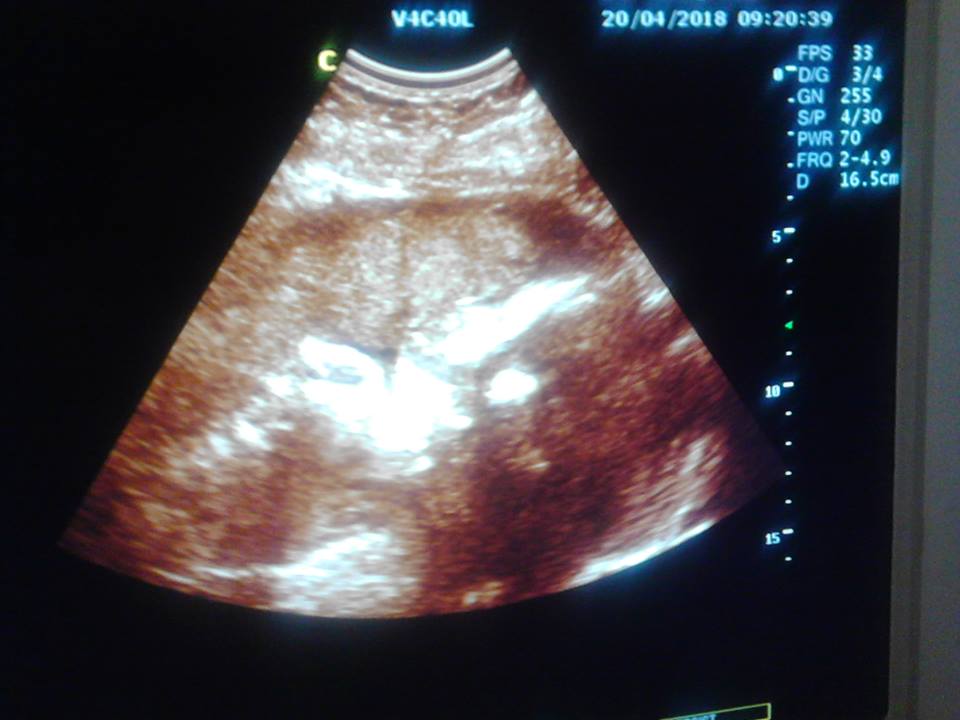

cryptocurrencies are changing lives, wonderful things have happened in my life within 2 months I'm going to become a living father in venezuela and hyperinflation has destroyed our quality of life, but thanks to steemit and the criptoactive mecados I have been able to buy food for my wife with 7 months of pregnancy and some clothes for the child, I still have many problems to solve, but I am confident that in the next few days we will be able to get ahead everything will improve!

is my first child, I had many feelings of fear, euphoria, sadness and happiness, I am very happy, my wife could not have children and it happened, the best thing is that the doctors indicate that the child is healthy, we are very eager to have him with us , I work a lot and my free time I spend in steemit everything I do for him I have faith that everything will be better !! thank you greetings